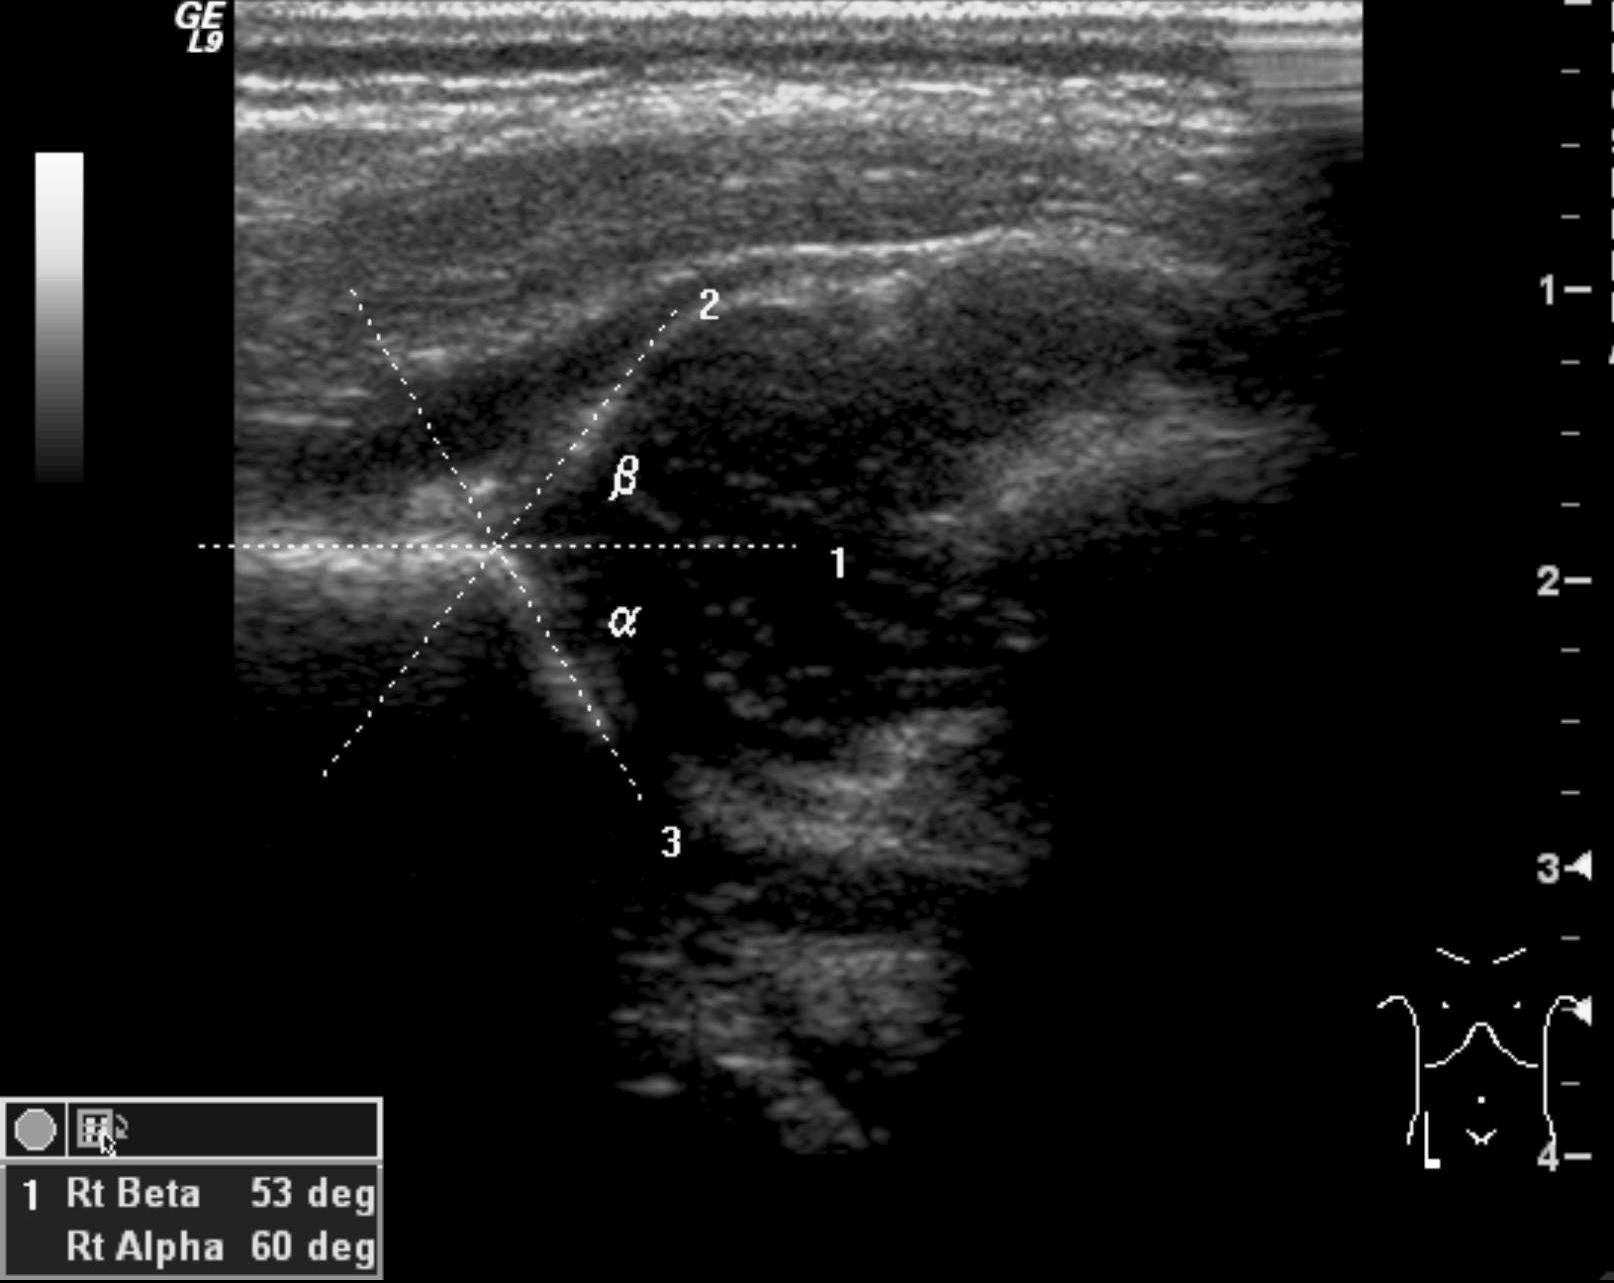

Hip dysplasia. Congenital hip dysplasia is a multifactorial disease that occurs more in girls (1:9) and causes the dislocation of the head of the femur. Acetabular rim development and configuration abnormalities, ligament looseness, muscle contracture, family history of hip dysplasia, or intrauterine breech position have all been mentioned as possible factors causing hip dysplasia. US examination is capable to diagnose infant hip dysplasia. It is indicated if the clinical examination raises suspicion or if risk factors (breech position, twin pregnancy, family history, oligohydramnion, deformed limb, neuromuscular disease) persist. US can be used as a screening tool. Due to the physiologic looseness of the ligaments before 4 weeks of age the hip is immature, therefore screening exam should take place after 4 weeks and can be performed until 4-6 months. X-ray exam: can only detect indirect signs of hip dysplasia until the appearance of the ossification centers of the femoral head.

Röntgenfelvétel: a csipődysplasia a csontos femurfej magjának megjelenéséig csak indirekt jelekből diagnosztizálható.

42. US examination. Normal newborn hip (arrow: hip bone.)